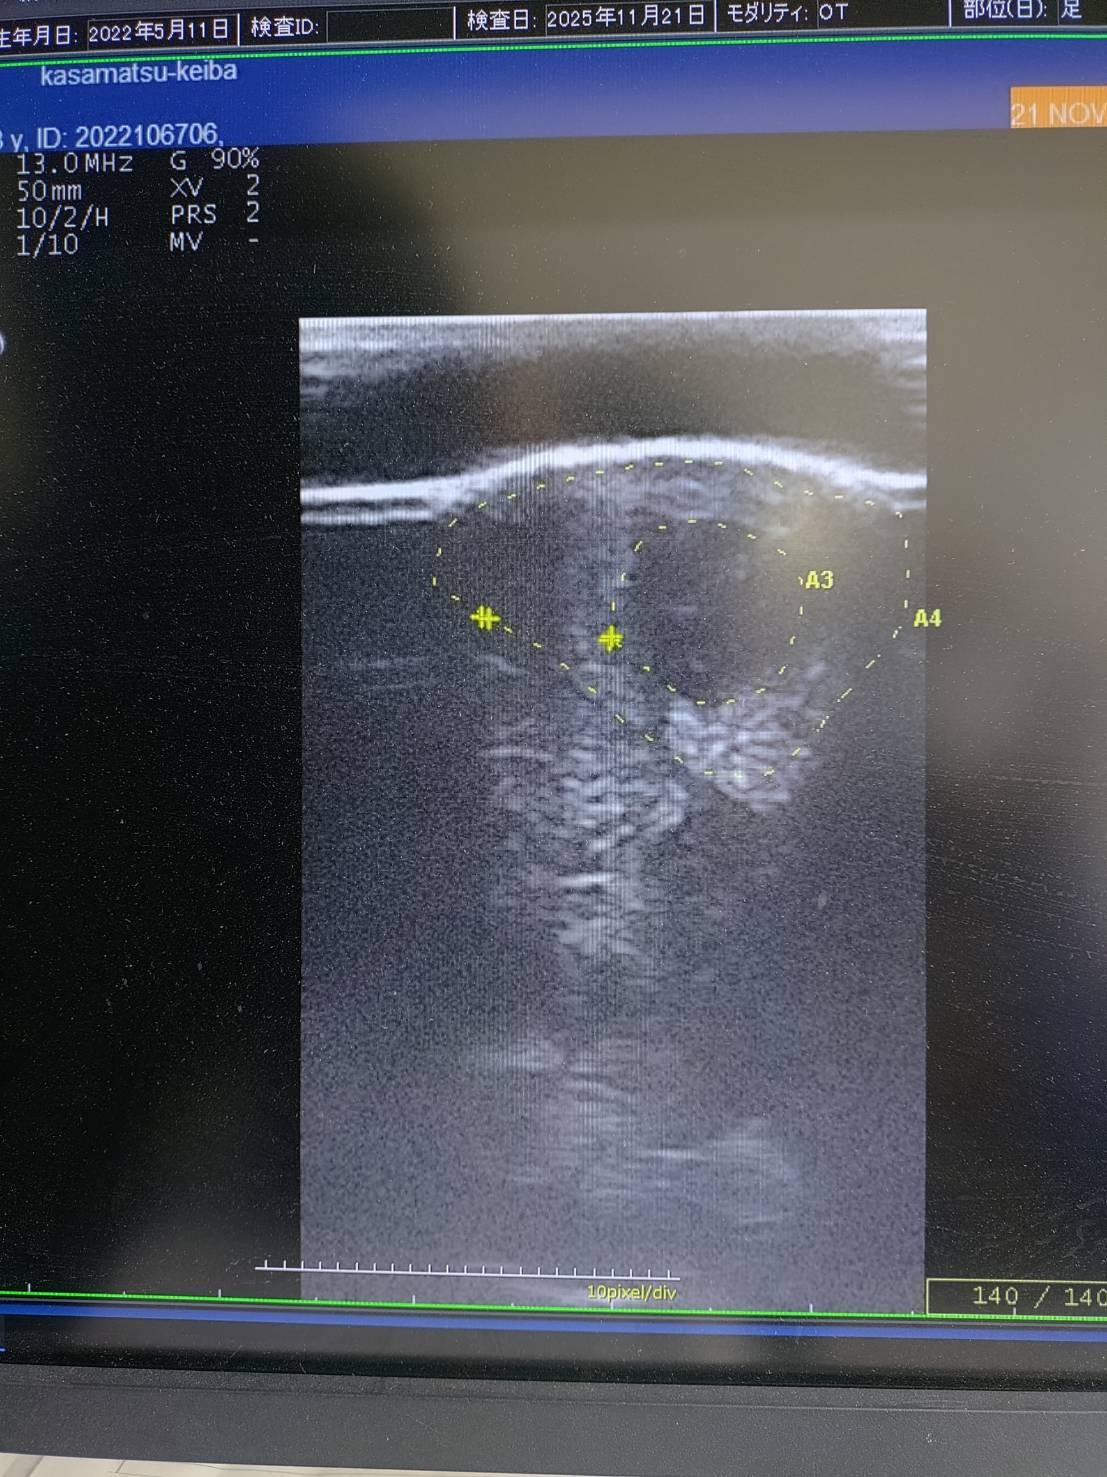

レース後に左前脚の浅屈腱炎発症が判明。損傷率はコア型の27%で全治にかなりの時間を要することからファンド解散となり、オークションへ出品いたしました。

18日のレース後、裏スジを腫らしていたのでエコー検査したところ、27%の損傷が確認されました。常歩の歩様は跛行を見せておりませんが、気持ち熱感はあります。惜しい競馬が続いており、初勝利までもう一歩という段階で無念です。(笠松競馬・後藤佑耶調教師)